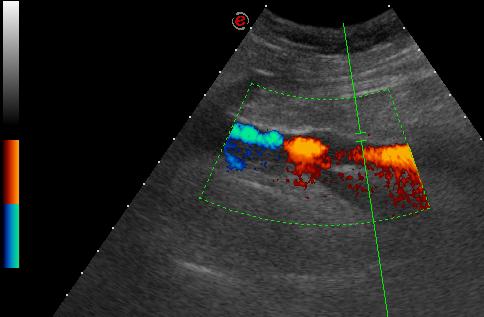

| …és coronalis síkban |

| kontrasztanyagos UH vizsgálattal látszik, hogy a kérdéses elváltozás vascularisatiot nem mutat |